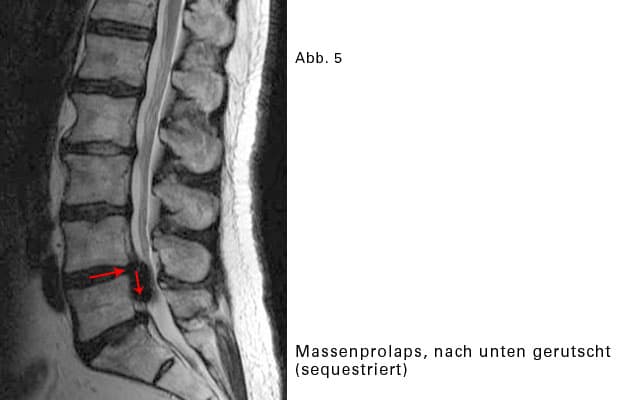

Sequestierter BSV:

Das vorfallende Gallertgewebe löst sich von der restlichen Bandscheibe und rutscht im Wirbelkanal etwas nach oben oder nach unten.

Massenprolaps:

Wenn sehr viel Material des Gallertkernes austritt, wird der BSV Massenprolaps genannt. Dadurch wird im Wirbelkanal sehr viel Platz beansprucht. Es wird sehr eng für sämtliche Nervenwurzeln, die an dieser Stelle vorbeiziehen. Mehrere Nervenwurzeln können gleichzeitig gequetscht werden. Das Beschwerdebild ist entsprechend vielschichtig. Glücklicherweise kommen Massenvorfälle selten vor.